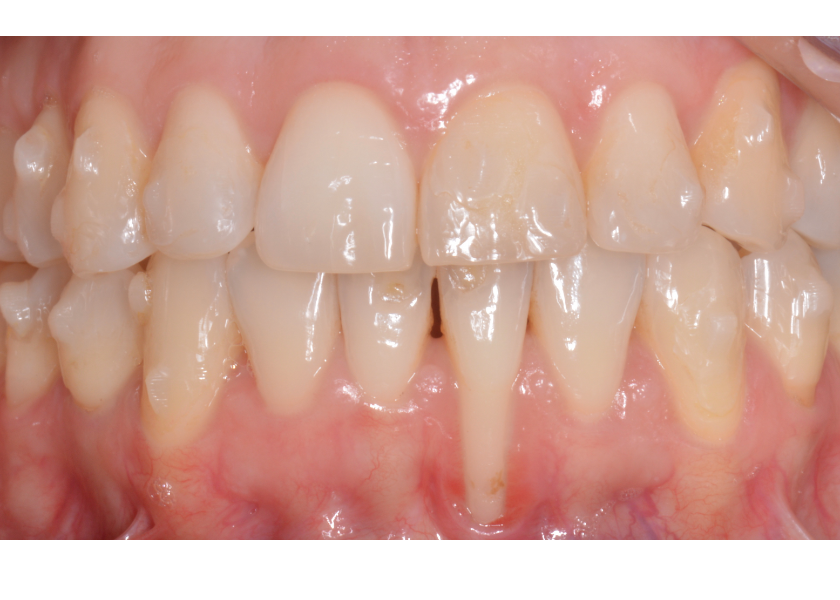

Paciente de 41 años que acude para hacerse un tratamiento de ortodoncia. Tras un incidente durante la ortodoncia una recesion existente en la pieza 31 se agrava.

La sensibilidad del paciente aumenta considerablemente y le molesta tanto el cepillado que impide su correcto mantenimiento.